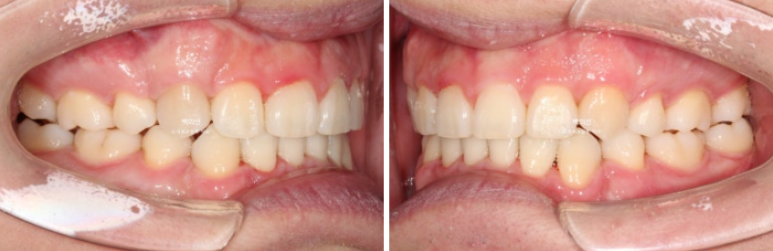

24년 10월, 돌출입 수술 한달 후 내원한 환자분 입니다.

24.10

돌출입 수술을 하면 수술 테크닉적으로 작은어금니가 있던 공간이 약 2mm 이상이 남게 됩니다.

송곳니 뒤쪽에 2mm 의 공간이 각각 남았습니다.

이렇게 애매하게 남은 공간을 앞니 배열을 위한 공간으로 사용하는 것이 돌출입 수술교정의 핵심입니다.

전 후 비교 보겠습니다.

24.10~25.08

앞니가 깊게 물리는 과개교합도 좋아졌습니다.